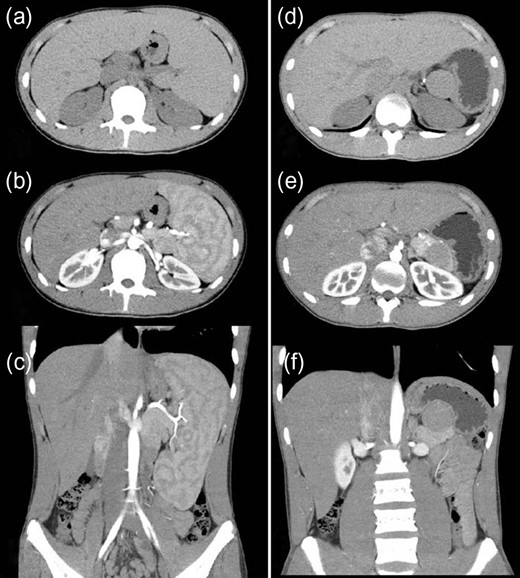

A 16-year-old boy was admitted with a rapidly growing pancreatic mass. He had received a diagnosis of HS based on the following: the need for a blood transfusion to treat anemia after birth, a history of hemolytic anemia, and a family history of HS. He had often undergone medical examinations for anemia and jaundice in junior and senior high school. When he was 15 years old, he visited our hospital because of the rapid onset of jaundice. Radiological examinations, such as computed tomography (CT) (Fig. 1a–c) and magnetic resonance imaging (MRI) (Fig. 2a–c), showed a huge spleen and a 2-cm mass near or in the pancreatic tail. Sonazoid-enhanced ultrasonography showed hypervascularity in the mass, which appeared to be located near the pancreatic tail and raised suspicions about an accessory spleen (Fig. 3a). The patient underwent a successful splenectomy by laparotomy, but the mass found on the preoperative examination could not be found by inspection and intraoperative ultrasonography (Fig. 4a and b). The mass grew rapidly to 4 cm one year after splenectomy, as shown on the radiological examinations (Figs 1d–f, 2d–f and 3b), but a recurrence of HS with anemia or jaundice did not develop. However, he underwent successful laparoscopic surgery to aid in the differential diagnosis. After the adhesions of the omentum to the abdominal wall were detached, the laparoscopic ultrasonogram revealed the mass in the pancreatic tail. He underwent laparoscopic distal pancreatectomy (Fig. 4c and d), and he had no clinical symptoms or signs of local infection or sepsis. A CT on the ninth postoperative day showed a small peripancreatic collection (Grade B: the clinical grading of postoperative pancreatic fistula). He was discharged on the 11th postoperative day. The resected specimen revealed the intrapancreatic mass that was covered with pancreatic tissues, and the intrapancreatic mass was an accessory spleen (Fig. 4e).

Magnetic resonance imaging (MRI) (before and after splenectomy). (a–c) Before splenectomy: MRI shows a huge spleen and a 2-cm mass in the pancreatic tail. (d–f) After splenectomy: MRI shows the mass in the pancreatic tail grows rapidly to 4 cm.